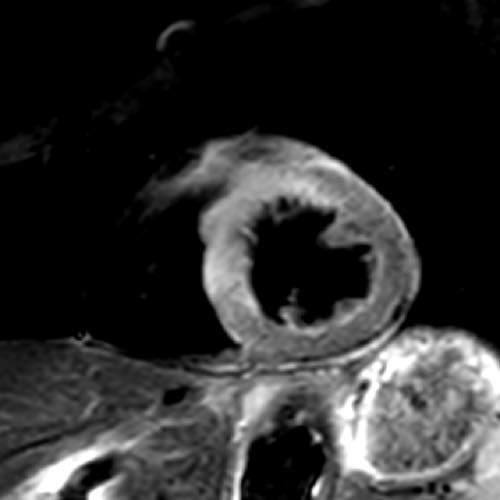

急性心筋梗塞の1例:シネMRI画像(左から中央)では、左心室の一部で収縮が低下している領域があり、心筋の浮腫(T2)画像では、同部位に信号値の高い部分を認め、急性心筋梗塞の所見となります。